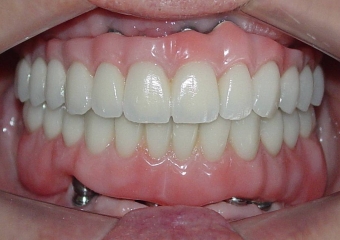

Sorriso do caso finalizado em maio de 2012